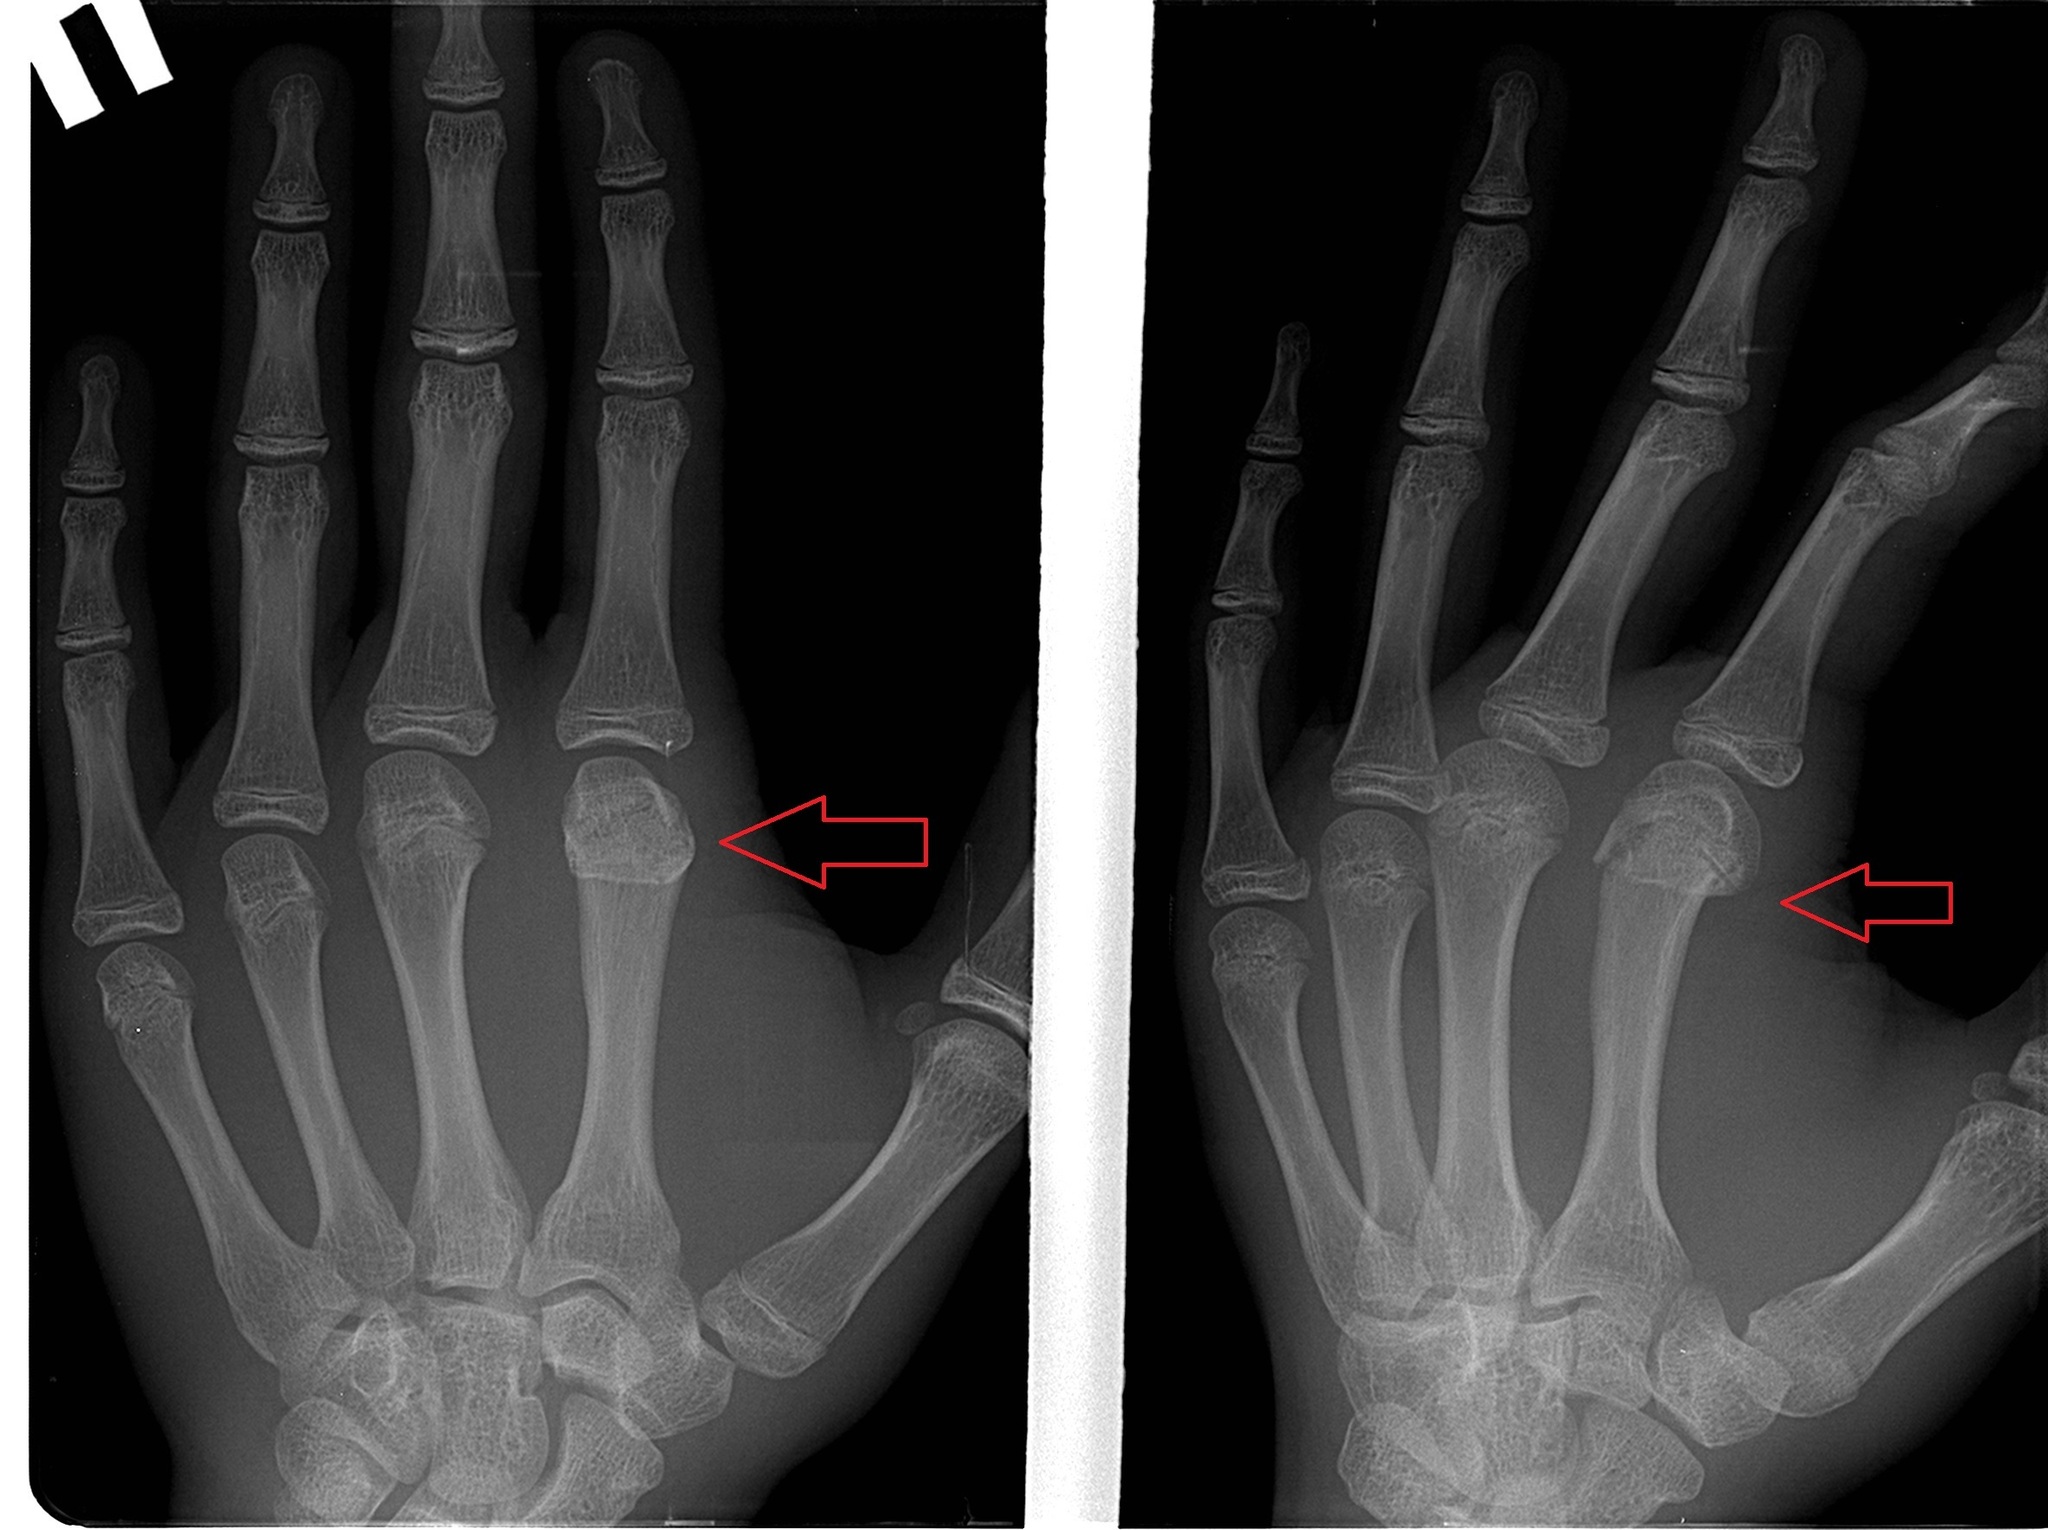

Отковыряв гипс от данного субъекта, отправляю его на снимок. И там *барабанная дробь*... Вопреки здравому смыслу, всё прекрасно сраслось!

P.S. Снимки прилагаю. Разница во времени между первым и вторым - 25 дней. Был еще снимок в чисто боковой проекции, но его как-то коряво сохранили и я не отыскал его в базе.